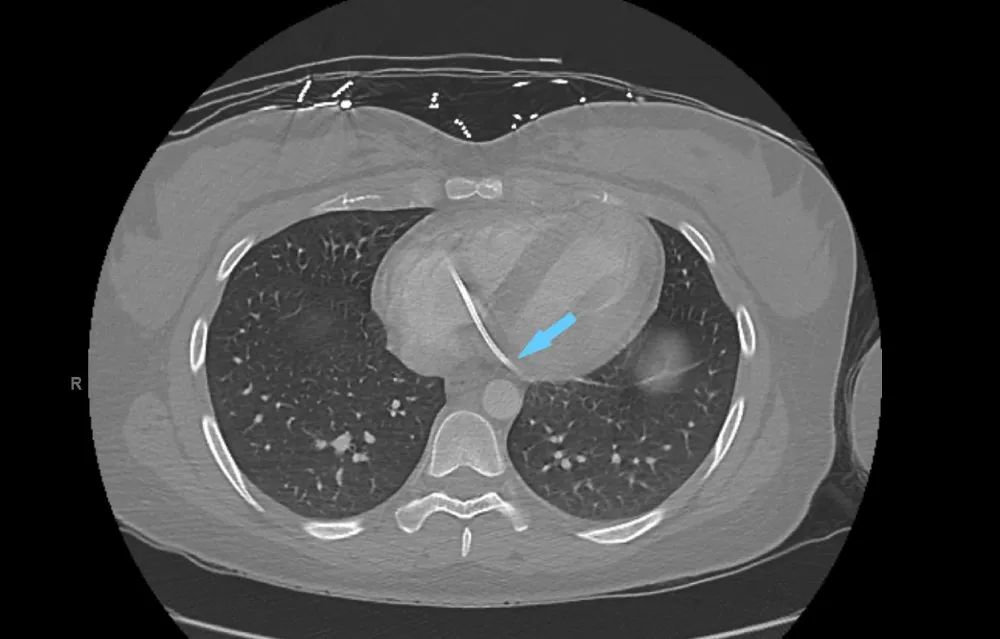

The patient underwent chest computed tomography, which showed that the fractured port migrated to the coronary sinus area of the right atrium (Figure 2).

Figure 2: Computed tomography of the chest shows a fractured port in the coronary sinus of the right atrium (blue arrow).